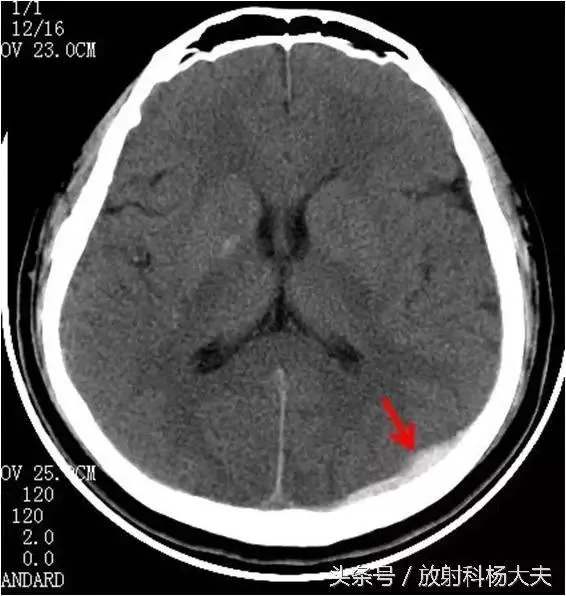

头部外伤后,第一次CT检查未发现异常,但一天后却出现了颅内出血,这种情况虽然罕见,却极其危险。2019年,一位35岁的男子在一次摩托车事故中头部受伤,当时CT检查未发现明显异常。然而,24小时后,他突然出现剧烈头痛、呕吐等症状,再次CT检查发现硬膜下血肿,紧急手术后才转危为安。

这种延迟出现的颅内出血,医学上称为“迟发性脑出血”。它之所以危险,是因为初期症状可能不明显,容易被忽视。随着时间推移,颅内压力逐渐升高,可能导致严重的神经系统损害,甚至危及生命。

迟发性脑出血的形成与颅内血肿密切相关。根据血肿的位置,可分为硬膜外血肿、硬膜下血肿和脑内血肿。其中,硬膜下血肿最为常见,约占颅内血肿的40%。这种血肿通常由连接大脑皮质和硬脑膜的静脉断裂引起,血液在大脑和硬脑膜之间积聚,压迫脑组织。值得注意的是,硬膜下血肿可分为急性、亚急性和慢性三种,其中慢性硬膜下血肿可能在受伤后数周甚至数月才出现症状。